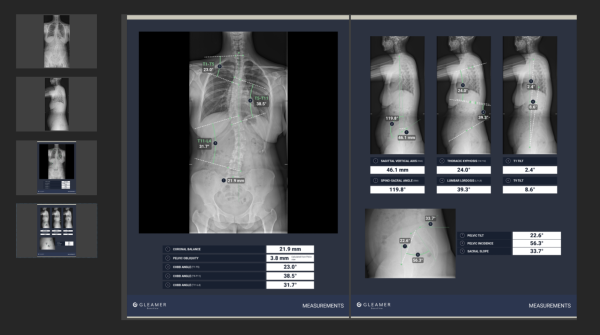

BoneMetrics ist ein KI-Assistent zur automatischen, präzisen Vermessung anatomischer Strukturen in Röntgen- und EOS-Aufnahmen (u. a. Becken/Hüfte, Ganzbein, Fuß, Wirbelsäule, Schulter, Knie, Babybecken).

Die Lösung automatisiert Routinemessungen, spart Zeit, reduziert Fehler und erhöht die diagnostische Genauigkeit.

KI-Standardisierung verbessert die Reproduzierbarkeit und optimiert die Befundung.